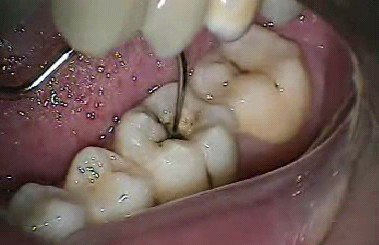

许多人牙齿出现问题,需要找牙医做窝沟封闭,牙齿这样医治之后,可以减少牙齿疼痛,同时也可以让周围牙齿得到保护。但是一些人做了窝沟封闭,出现掉了情况。有这种情况发生,不知道如何是好,下面一起来了解一下吧!看看窝沟封闭2天掉了怎么办?

如果做了窝沟封闭之后,需要每隔半年到医院检查1次,发现只要封闭剂能够完整存在才能起到防龋的作用。若是封闭材料发生脱落,需要马上重新封闭,然后再定期检查。注意酸蚀不会持续起作用,而且因为窝沟比较深,清洁不容易,就会发生清洁不彻底,待明确检查为了预防龋齿形成还是需要继续窝沟封闭,若是形成浅龋也要及早充填。

做了窝沟封闭后,也不是一劳永逸的,需要每半年到医院做一下检查,需要查看一下窝沟封闭还完整吗,若是有脱落,需要重新进行封闭。为了不影响窝沟封闭,人们在日常需要注意做好保护工作,尽量不要咬硬物,再就是做窝沟封闭建议选择好的材料。